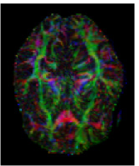

The first eigenvector , also called principal diffusion vector, of describes the predominant diffusion direction, which is parallel to the orientation of the corresponding underlying WM fiber system. Figure 3 shows a visualization of the color-coded MR-DTI data with ellipsoids. The predominant diffusion direction can be directly related to a Green (G), Red (R) and Blue (B) digital color triple. The convention in which the G, R and B color components represent the directions is as follows:

| (6) |

The RGB color-coded directionality maps provide an indication of the direction in which water diffusion is the highest and improve the visibility of different WM fiber bundles.

![]() |

| (a) | (b) | (c) | (d) |